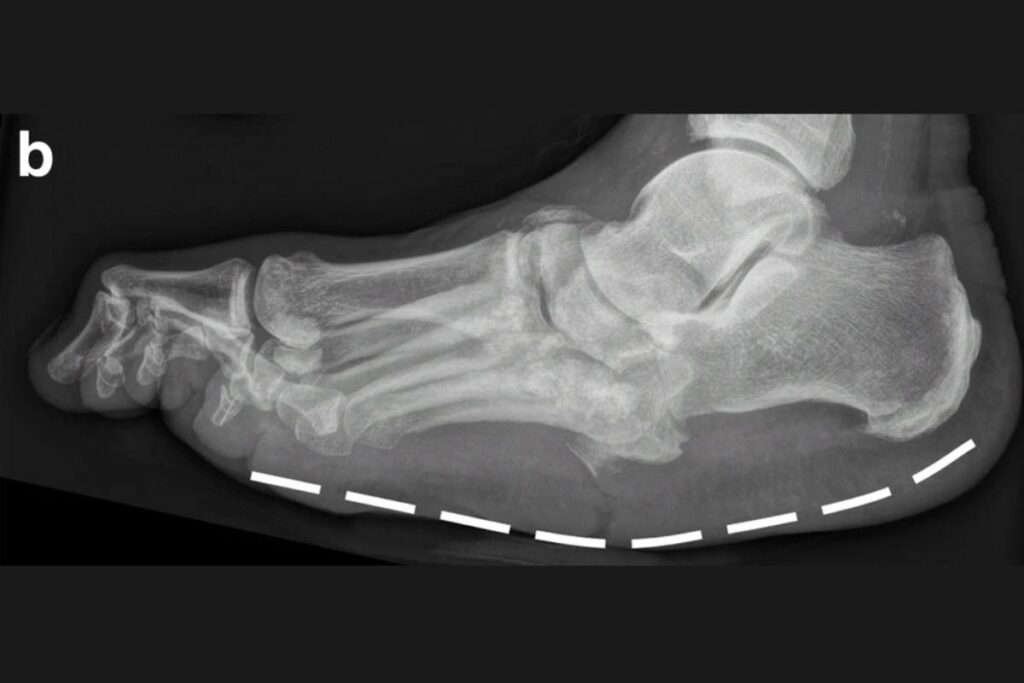

Imagens clínicas e de radiografias demonstrando um paciente com Artropatia de Charcot. Fonte: DOI: 10.1186/s13244-019-0768-9

Exemplo de artropatia de Charcot – Fraturas diversas em processo de consolidação nos óssos do médio-pé.